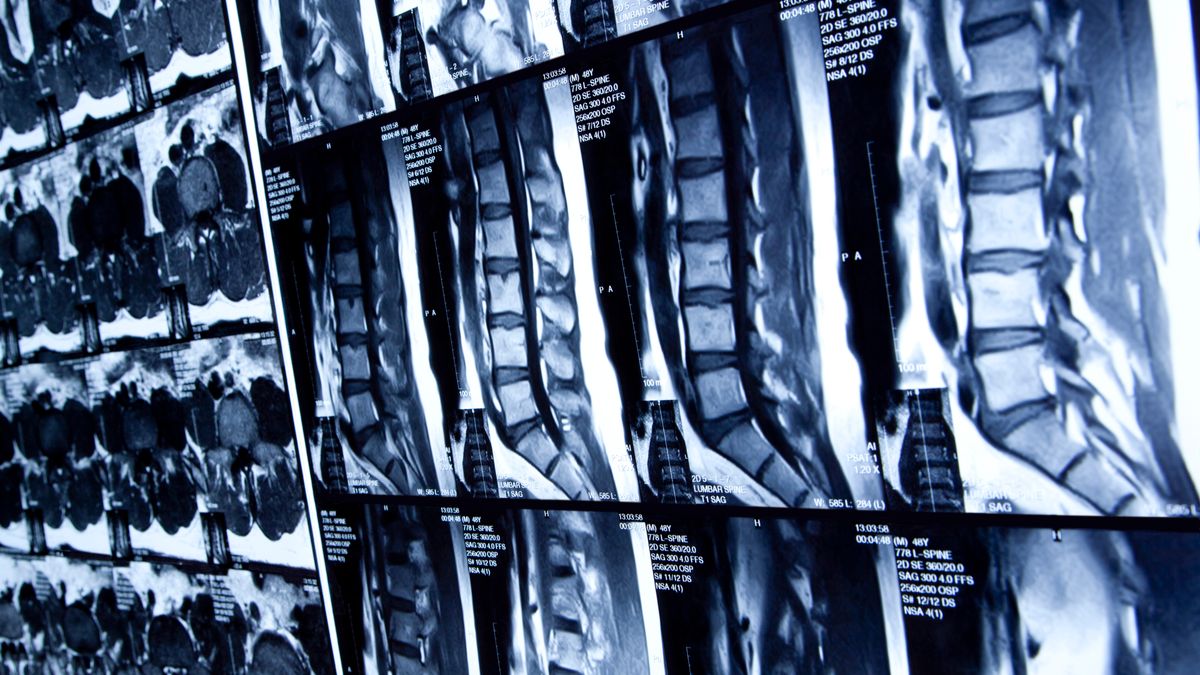

Zimvie to sell spine business for $375M

Zimvie announced plans on Monday to sell its spine business to Miami-based investment firm H.I.G. Capital, narrowing the company’s focus to its dental business.